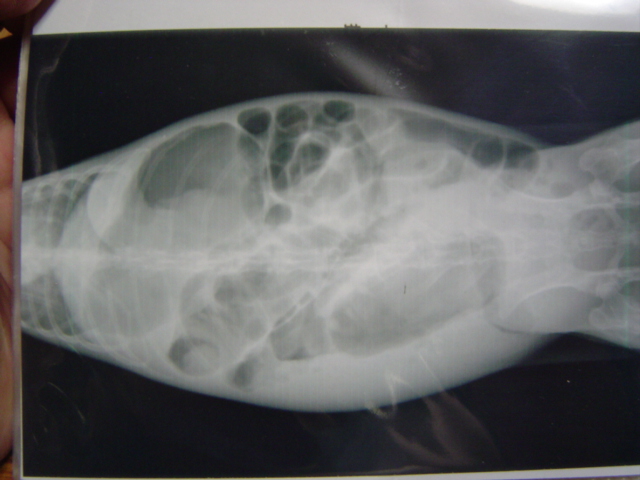

レントゲン

腸にガスが溜まり盲腸便秘を起こしている。